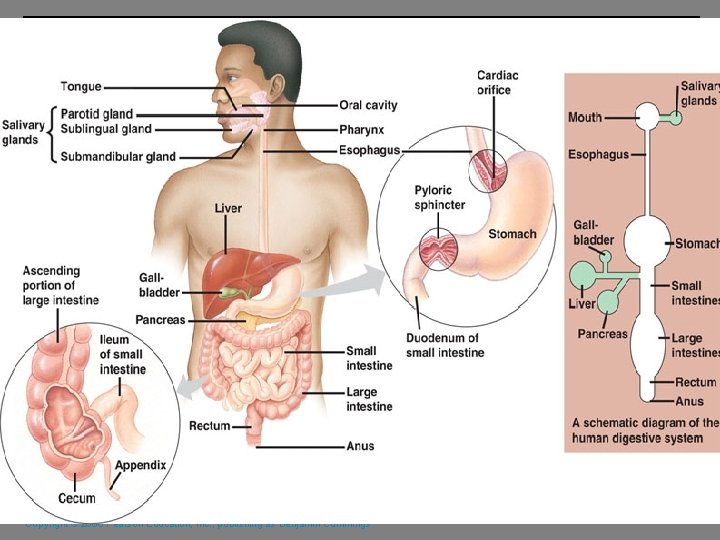

Digestive System Brainstorm what each of the following organs/structures does regarding digestion: § § § The alimentary canal or gastrointestinal (GI) tract digests and absorbs food Alimentary canal consists of – mouth, pharynx, esophagus, stomach, small intestine, and large intestine Accessory digestive organs – teeth, tongue, salivary glands, liver, gallbladder and pancreas Copyright © 2006 Pearson Education, Inc. , publishing as Benjamin Cummings

Digestive Process § The GI tract is a “disassembly” line § § Nutrients become more available to the body in each step (example: proteins broken into amino acids) There are six essential activities: 1. Ingestion 2. propulsion by peristalsis 3. mechanical digestion 4. Chemical digestion 5. absorption 6. defecation Copyright © 2006 Pearson Education, Inc. , publishing as Benjamin Cummings